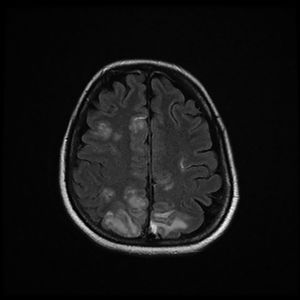

The patient was discharged to the ward on the fifth day, where inattention, apathy, and asymmetric mobilization of the right lower limb were noted. Although she showed steady respiratory and neurological improvement, a magnetic resonance imaging (MRI) study reported extensive hyperintense areas involving both the cortex and subcortical white matter. These areas were bilateral and symmetrical, but with greater extension in the right hemisphere and involvement of the parasagittal region and the bilateral parietal convexity, the bilateral frontal parasagittal region, and areas in the region of the right frontal superior convexity. Small areas of leptomeningeal uptake were identified, corresponding to slower, though unrestricted, intravascular blood flow. The finding was reported as posterior reversible encephalopathy (PRES) (Figs. 3 and 4). After the third day of hospitalisation, the patient presented episodes of HT, which were initially treated with labetalol and later with enalapril and amlodipine, and were diagnosed as peripartum hypertension. Nine days after re-admission to the ward the patient was discharged home after a total hospital stay of 18 days. Enalapril, amlodipine, and levetirazetam were prescribed as outpatient treatment.

Magnetic resonance imaging (T2-weighted and FLAIR images): Axial slices showing hyperintense areas with bilateral cortical and subcortical white matter involvement, more extensive in the right hemisphere. Involvement is seen in the parasagittal region and bilateral parietal convexity, and in the bilateral frontal parasagittal region. The image is suggestive of PRES.

None of the published cases of encephalitis have reported EEG results. Though nonspecific, the findings in our patient are compatible with viral encephalitis. Thromboembolism (common in COVID-19 patients) and cerebral haemorrhage/ischaemia had previously been ruled out with CT and angioCT without contrast. The MRI performed 2 days later (Figs. 3 and 4) with T1-weighted sequence in the sagittal plane and in T2 and FLAIR in the axial plane was compatible with PRES.